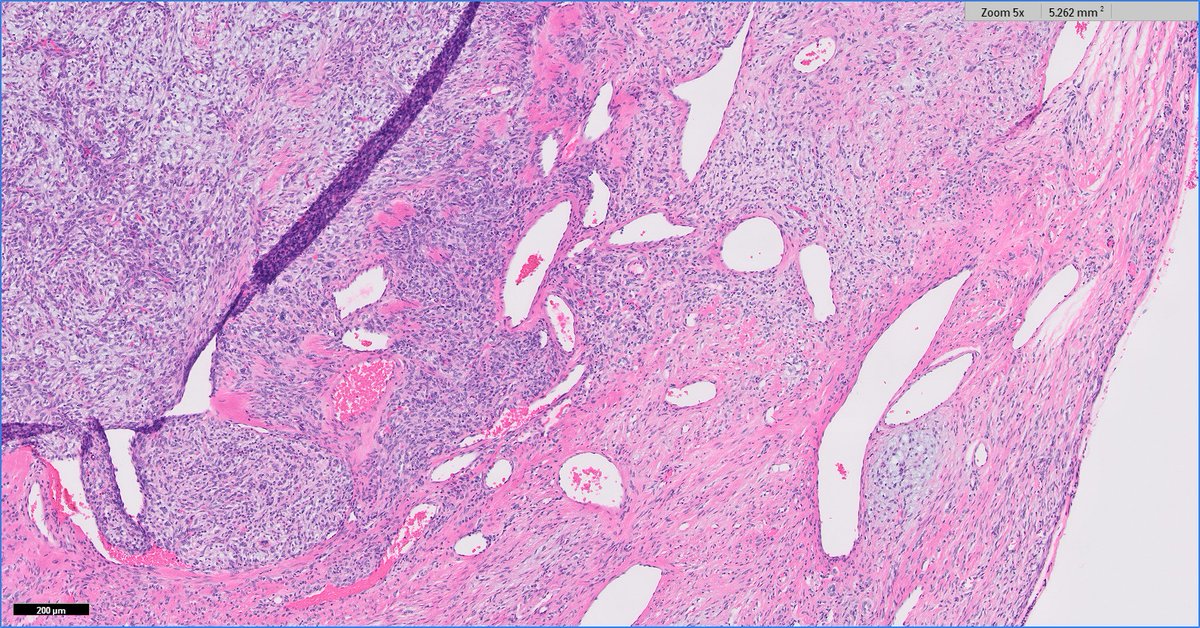

Anatomical Pathologist - UBC #BSTpath #GYNpath